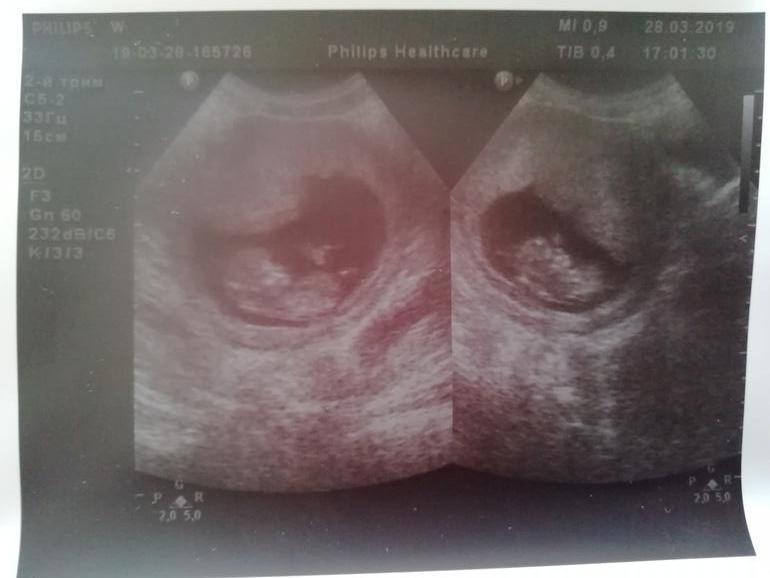

Результаты: УЗИ, КТГ, доплера, скринингаПрошли мы первый скрининг все ттт... Хорошо.

Малыш развивается быстро опережает на несколько дней.

КТР - 45.0мм. Сердцебиение хорошое 164 уд. м

Прикреплены мы по передней стенке.

Вес малыша 49 гр.

Дали нам фоточку.

Какой же он маленький человечек. Ребёнок очень активный, как начали смотреть закрыл кулаками лицо. Показали мне все до мелочи, поститали пальчики, показали пуповину. Эмоции лезли через верх

А вот и мы